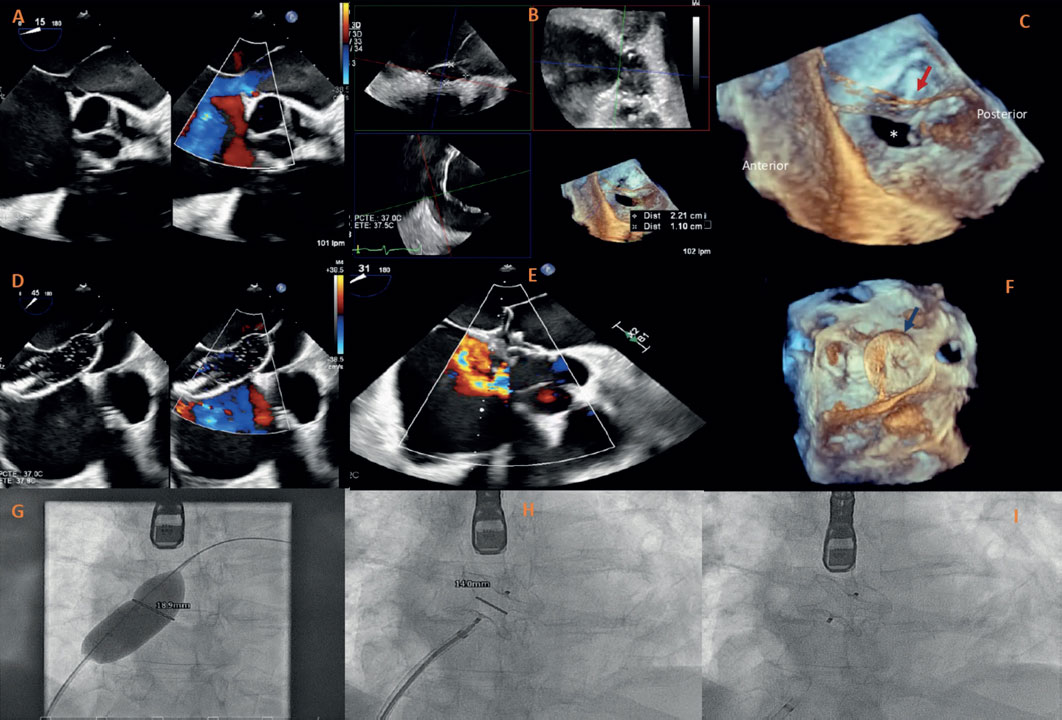

This is the case of a 67-year-old man with signs of right heart failure due to an atrial septal defect (ASD) with right ventricular dilation, significant left-to-right shunt (Qp/Qs 1.5), and no significant pre-capillary pulmonary hypertension (mean pulmonary artery pressure, 26 mmHg; pulmonary vascular resistance, 2UW). Three-dimensional transesophageal echocardiography (3DTEE) revealed the presence of a cor triatriatum sinister (CTS) with a membrane extending from the upper-posterior end of the fossa ovalis to the pulmonary ridge, with multiple fenestrations, the largest measuring 24 mm (figure 1A). A 22 mm × 11 mm ostium secundum ASD was confirmed with the posterior rim partially covered by the membrane (figure 1B,C). Since the patient was technically suitable and had increased surgical risk due to cirrhosis, a percutaneous approach was undertaken. The procedure was performed under 3DTEE and fluoroscopy guidance, a 0.035-in guidewire and multipurpose catheter crossed the ASD, balloon sizing confirmed a 20 mm defect, and an 24 mm Amplatzer septal occluder (Abbott Structural Heart, United States) was successfully implanted (figure 1D,F). TEE confirmed accurate device placement, with no residual shunt and no left atrial flow obstruction. Informed consent was obtained.

Figure 1.

CTS is a rare cardiac malformation that can coexist with ostium secundum ASD in up to 33% of patients. Although transcatheter closure is preferred in suitable anatomies, the presence of CTS can complicate the device deployment due to inadequate margin definition, with increased risk of device instability and embolization. In this scenario, ASD closure was particularly challenging as the posterior rim was in direct continuity with the atrial membrane, raising concerns about proper device apposition. This case highlights the importance of advanced imaging, such as 3DTEE, in complex anatomies by allowing precise procedural planning and real-time guidance to ensure a successful intervention.